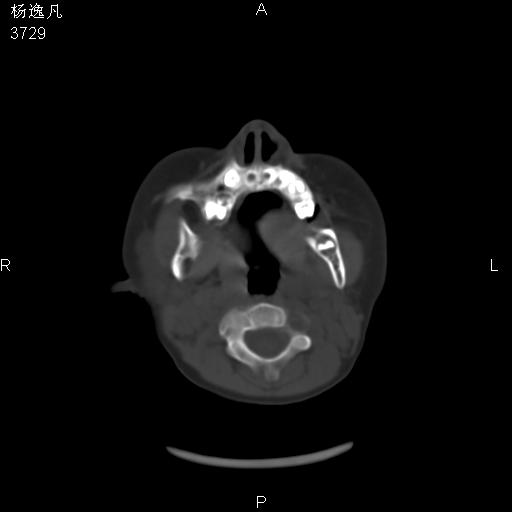

男性,5岁,面部受外伤,余无特殊

骨窗

1、右面部及颞部软组织肿胀。

2、腺样体肥大。

头颅ct平扫未见明确外伤性征象,右侧面部及颞部软组织肿胀,后鼻腔软组织影增大,增厚,鼻咽顶部变窄,考虑鼻咽腺样体增值肥厚。

双侧位置太不对称,未见明显骨折征象。